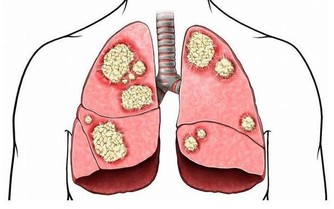

簡單來講骨質疏鬆症是骨代謝的異常(人體內破骨細胞影響大於成骨細胞,以及骨吸收的速度超過骨形成速度)造成的。

所以,骨質疏鬆症的治療不是單純補鈣,而是綜合治療,包括提高骨量、增強骨強度和預防骨折等。也就是說,調整飲食、合理用藥、堅持鍛煉、做好防護,這些措施都要有。